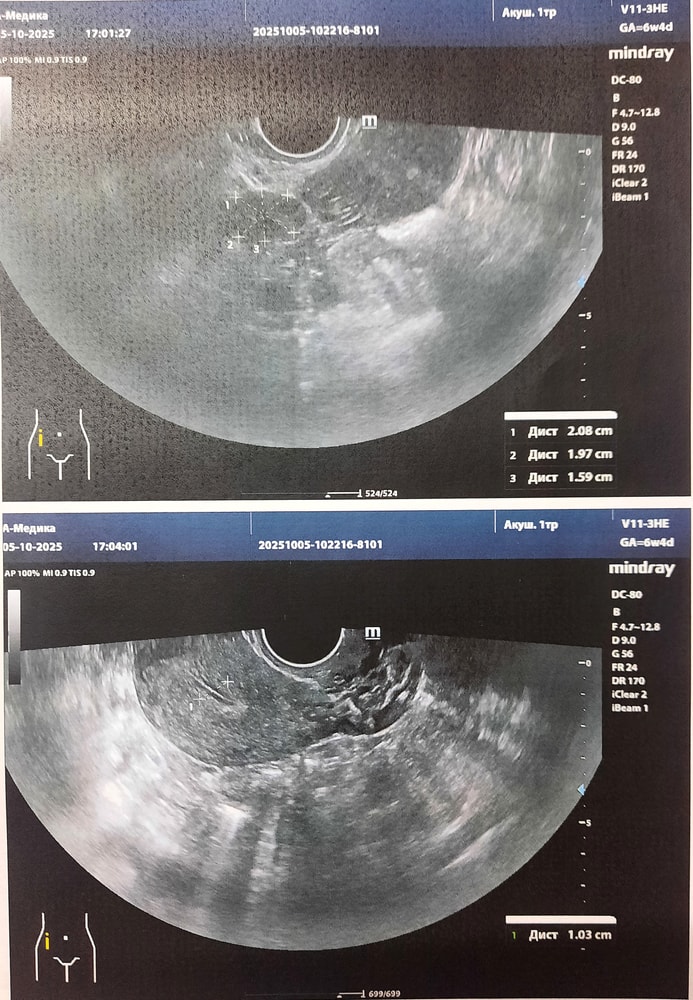

5.10 - боль продолжается, на узи опровергли овуляцию, сказали в остальном всё чисто и прекрасно, болеть там нечему, это кишечник.